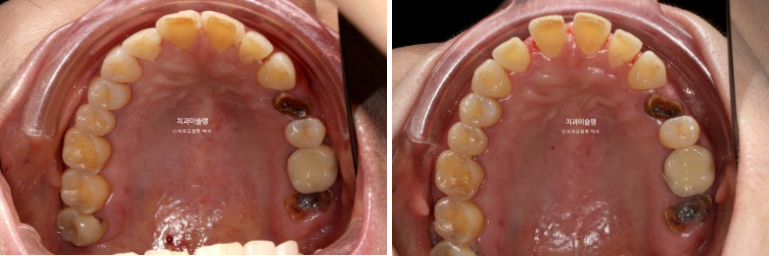

24.07~26.01

아래 앞니는 치간삭제와 함입으로 위 앞니 사이사이 벌어진 공간을 이용하여 뻗친 각도와 골출을 개선하였으며

위 아래 앞니 각각 1.5-2mm 가량 뒤로 들어갔습니다.